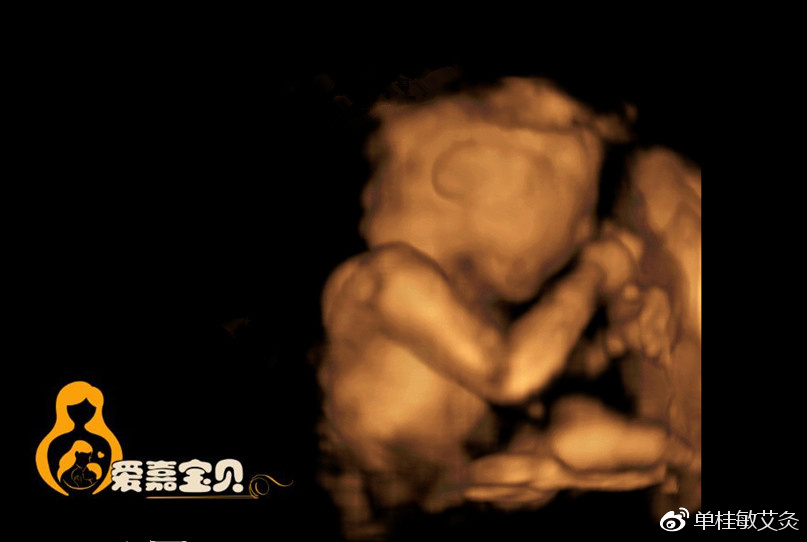

那么张晓毓这个糖尿病指标就已经高出了很多很多。前些日子她怀孕了,怀孕以后,由于她糖尿病指标非常高,到北京妇产医院去做产检,医生,护士,专家会诊,就让她把孩子做掉,她在那住院,大夫护士轮流轰炸,让她把孩子做掉,然后说,孩子致畸率有多高多高,产妇的高风险率有多高多高?

当时我就说你的指标从小就这样,你下次怀孕仍然是这样,难道你一辈子不怀孕吗?如果是我,我坚决留下,就这样在我左说右说,把孩子留下来,到现在怀孕六个月了,孩子很好,检查三维四维,所有的指标都健康,如果当初不是我死乞白赖的让她留下这个孩子,那么还不一定会怎么样呢?哪些检验指标真的是那么重要吗?难道不看人的自身状态,净看指标下药这样的治疗安全吗?